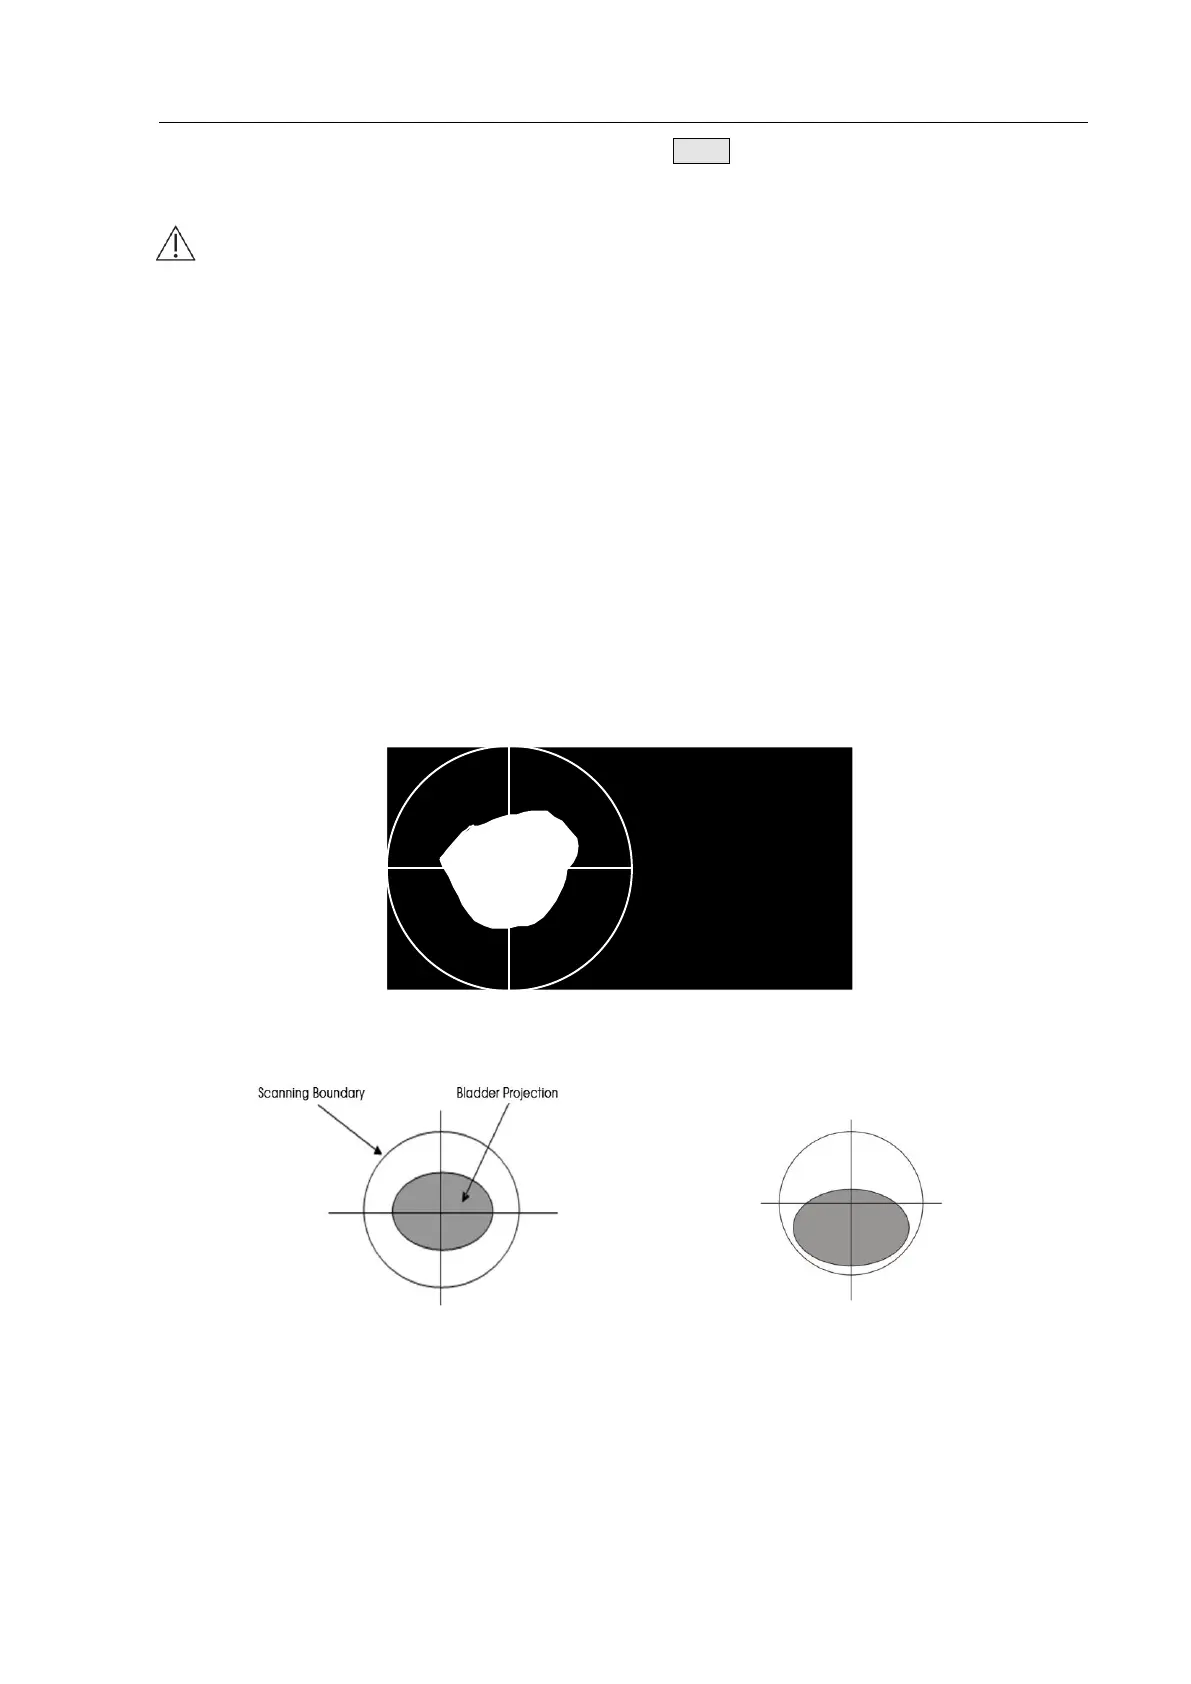

4.2.4.4 Bladder Projection Image

To determine whether the measurement position is correct, after scanning, the device switches to

the bladder projection interface which can display the bladder projection image, as shown in Fig.

4.18a. If the projection is close to roundness, basically located in the center of the scanning area,

and does not exceed the scanning boundary, as shown in Figure 4.18b, then the position of the

Main Unit is correct and the measured volume value is valid; otherwise, you should adjust the

position of the Main Unit and measure again.

Fig. 4.18a Bladder Projection Image

Fig. 4.18b Correct Position Fig. 4.18c Incorrect Position

Fig. 4.18b: The bladder projection is basically located in the center of the scanning area,

close to roundness, and does not exceed the scanning boundary.

Fig. 4.18c: The bladder projection is beyond the center of the testing area, the

measurement result is inaccurate and re-measurement is required.